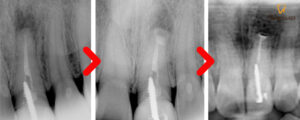

울산남구치과 정기검진 차 오셨을 때

예후를 보기 위해 X-ray 사진을

촬영해 보았는데요.

치근단 절제술 후에는 경과를 지켜 보며

치조골이 차오르는지 확인해보아야 하며,

현재 환자분께서는 간헐적으로 올라오던

볼록한 염증도 더이상 나타나지 않는다며

좋아해 하셨습니다.

후에도 정기 검진 예약을 잡아드려

경과를 관찰하기로 한 후

치료를 종결하였습니다.